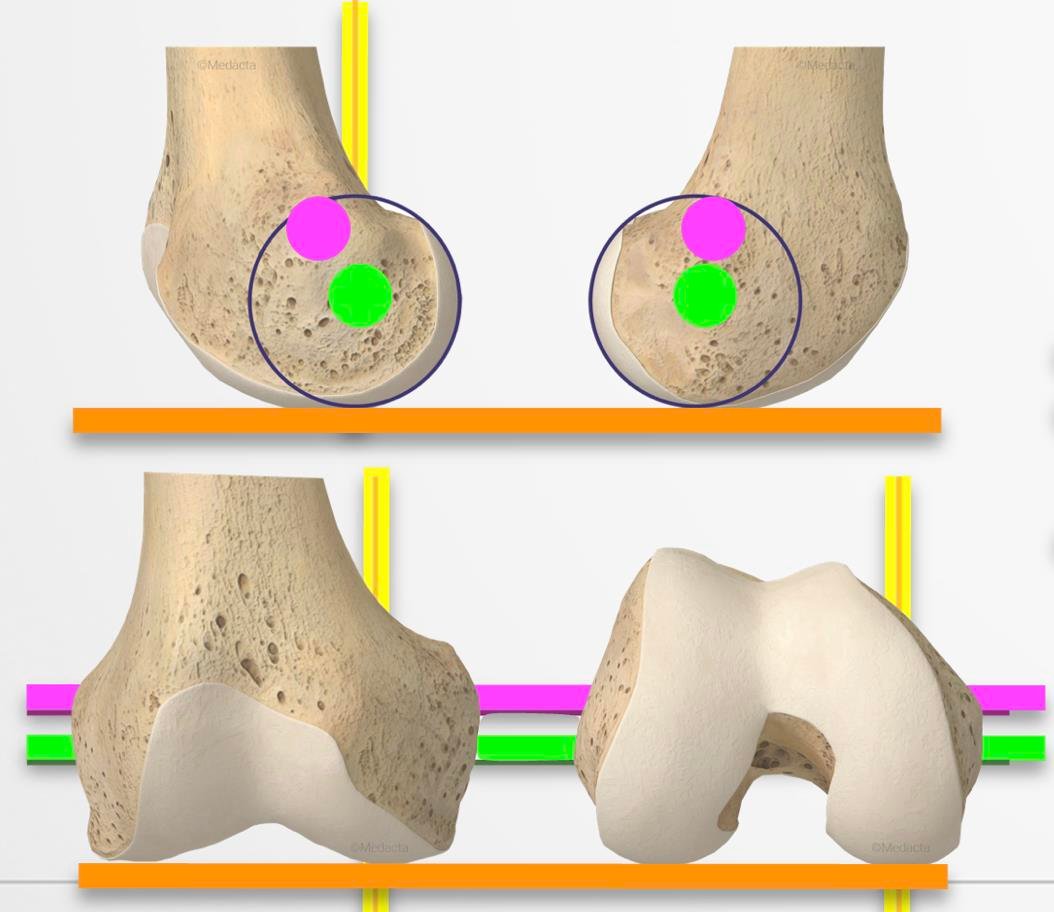

What is kinematic alignment and why is it important?

Traditional knee replacement surgery often uses a mechanical alignment technique, which places the implant in a neutral position relative to the body’s axis. While this method works well for many patients, it does not always match the natural alignment of an individual’s knee.

Kinematic alignment aims to restore the knee to its pre-arthritic position by closely matching the patient’s natural bone and joint lines. Instead of creating a standardised joint shape, the implant is positioned to mirror the original anatomy as much as possible.

Potential advantages of kinematic alignment include:

- A more natural-feeling knee joint after recovery

- Improved knee movement and flexibility

- Reduced need for ligament releases during surgery

- Increased patient satisfaction, particularly in everyday movements

This approach is carefully planned using pre-operative imaging and may be combined with robotic technology to further enhance precision.

Imaging: X-rays, CT scans, and 3D modelling

Your surgical journey begins with diagnostic imaging. Standard weight-bearing X-rays are usually the first step, helping to assess the degree of joint damage, alignment, and the condition of surrounding bone structures. In some cases, advanced imaging such as CT scans or MRIs may be used to build a more detailed picture of your knee.

Many modern knee replacement techniques now incorporate 3D imaging and modelling to support surgical planning. These images are used to evaluate the mechanical and kinematic alignment of your joint, and to understand how the bones, cartilage, and soft tissues move together. Accurate imaging provides the foundation for patient-specific alignment and implant positioning.